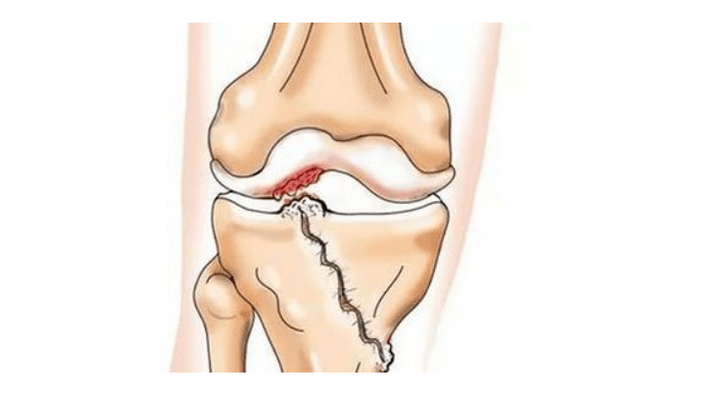

- Verletzungen (Frakturen, Meniskusrisse und vorderes Kreuzband). Leider führen diese Verletzungen bei jedem, unabhängig vom Alter, zu einer übermäßigen Belastung des Knorpels. Ein Bruch eines mit Knorpel bedeckten Knochenteils geht mit der Bildung einer Unebenheit einher – einer „Stufe“. In diesem Bereich kommt es bei Bewegung zu Abschürfungen und es bildet sich Arthrose;

- rheumatoide Arthritis, Morbus König (Osteochondritis dissecans), Folgen einer eitrigen Gelenkentzündung (Gonitis) usw.;

Die Ursache liegt meist in einer Subluxation, Fraktur oder Lateralisierung der Patella.